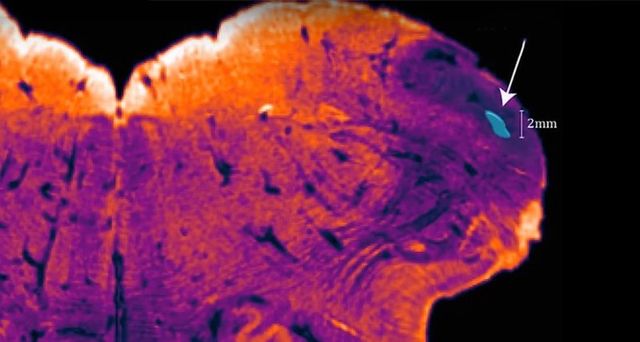

Нейробіологи, ретельно вивчаючи людський мозок при роботі над новим нейроанатомічним атласом, виявили раніше невідому ділянку, яка, можливо, є тільки у людей.

Нову ділянку виявила група дослідників з Австралії на чолі з нейробіологом Джорджом Паксіносом (George Paxinos). Цю ділянку вирішили назвати endorestiform nucleus, так як вона розташована всередині нижньої мозочкової ніжки (inferior cerebellar peduncle). Вона розташована біля основи мозку – поруч з областю, де вже починається спинний мозок.

Нижня мозочкова ніжка подібна річці, що несе інформацію від спинного мозку і мозкового стовбура до мозочка. Це група нейронів, яку можна порівняти з островом в цій річці, – пояснює Паксінос

Паксінос з іншими дослідниками зміг підтвердити існування endorestiform nucleus, використовуючи відносно нову техніку фарбування, розроблену для отримання більш чітких зображень мозкових тканин. Зображення були необхідні Паксіносу для складання нового нейроанатомічного атласу.

Розташування endorestiform nucleus наводить Паскіноса на думку, що ця область задіяна в дрібній моториці. У інших приматів ця ділянка поки не була виявлена, і можливо, endorestiform nucleus є черговою унікальною рисою людської нервової системи. Втім, це поки стверджувати рано: перевірити ідею Паскінос розраховує у майбутніх дослідженнях мозку шимпанзе.